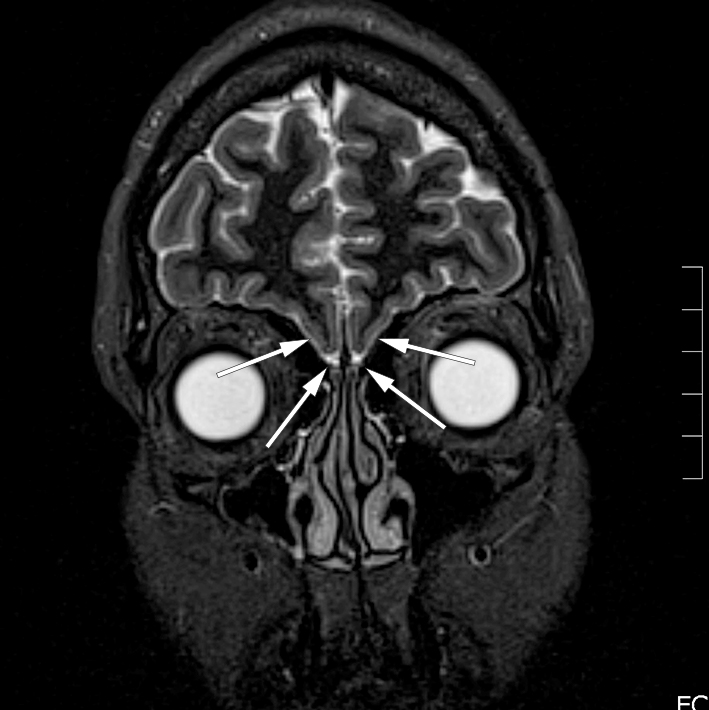

In this article we present the case of a patient admitted to the otorhinolaryngology department for examination of a reduced sense of smell. The patient had total anosmia. She explained that she had not reached puberty until first taking contraceptive pills. An hormonal test detected decreased levels of follicle-stimulating hormone and oestradiol. Anosmia combined with delayed puberty should raise suspicion of Kallmanns syndrome. MRI of the head confirmed the diagnosis, showing a complete lack of olfactory sulcus and bulbus bilaterally.

Anamnese med anosmi, manglende pubertetsutvikling og lave nivåer av kjønnshormoner før substitusjonsbehandling gav mistanke om Kallmanns syndrom, og hun ble henvist til ny MR caput med spørsmål om sulcus olfactorius og bulbus olfactorius var til stede. MR viste mangel på disse bilateralt (figur 1). Anatomiske forhold var dermed best forenlig med Kallmanns syndrom. Hun ble henvist til genetiker og endokrinolog, som ikke fant annen relevant patologi.